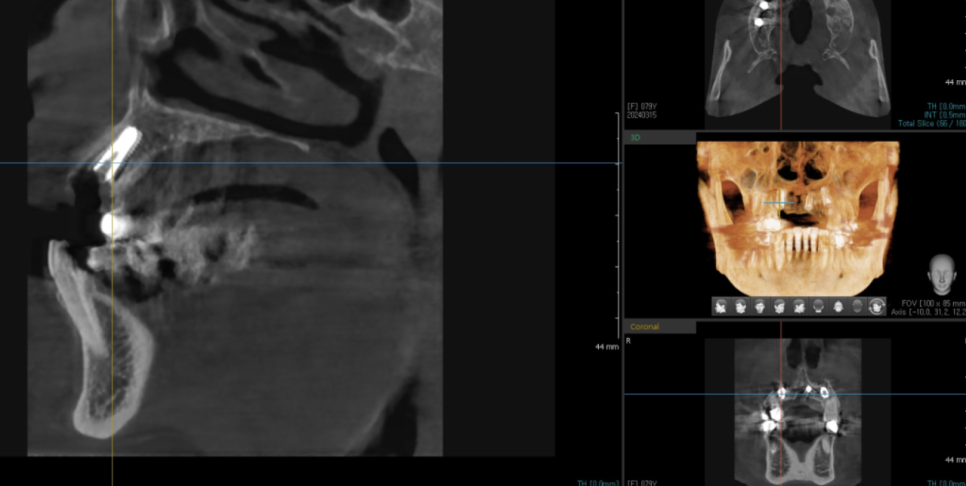

하남미사치과에서 앞니 임플란트 수술을 하셨는데요.

수술 과정에서 ct를 찍으면서

조심스럽게 진행하였습니다.

그 이유는,,,

24.03.15

앞니는 잇몸과 뼈가 얇아서

임플란트를 심을 공간이 안나올 때가 많습니다.

단순히 공간만 안나오는게 아니고

임플란트와 뼈가 잘 안붙을 수도 있는 문제다보니ㅠㅠ

하남미사치과에서는 이럴때를 위하여

미리 대비를 해두었죠!

앞니 전용 임플란트를 준비해두고

사용중인데요